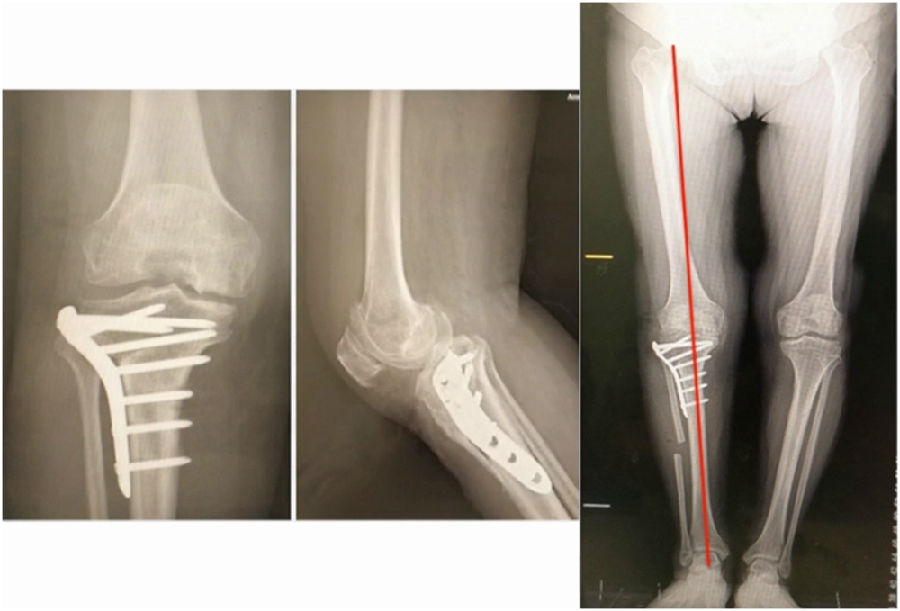

术后X线

结合影像学来看,该患者单纯用闭合截骨或开放截骨,对肢体均有影响,所以决定采用混合型截骨。术中混合截骨旋转中心选在内外1/3处,先做闭合楔,然后顺势将开放楔敲开,达到术前设计的目标力线。术后随访力线达到要求。